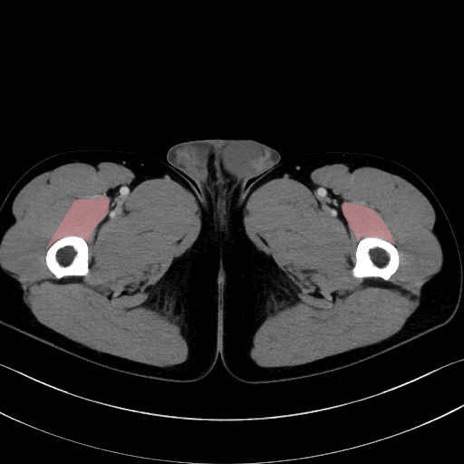

中間広筋 (Vastus intermedius)